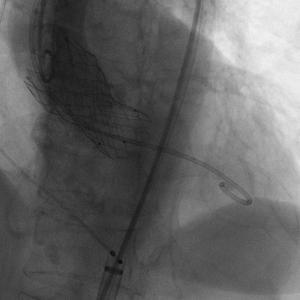

患者插管后已可以耐受造影剂,常规左侧作为辅入路进行操作,翻山造影后进行穿刺等操作,患者辅入路植入猪尾造影,根据造影调整体位使无窦,右窦,左窦分离,右窦居中,三个窦保持在同一平面,之后常规跨瓣进行后续操作。

主动脉根部造影